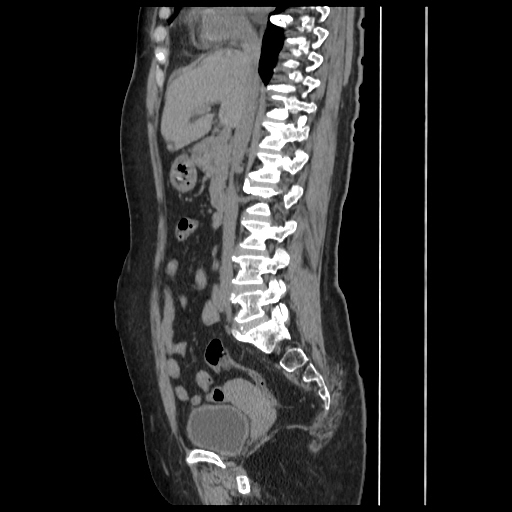

A CT abdomen revealed a left adrenal cortical tumor.

CT images: